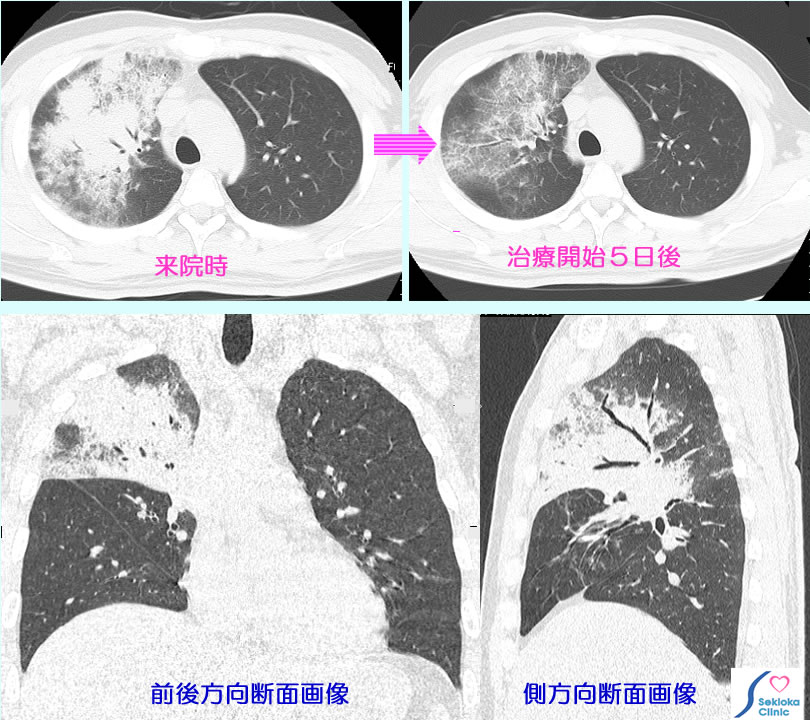

| 診断 | 肺の聴診で多くは疑いを持ち、胸部X線撮影。さらに、CTで正確な病巣の広がり、肺炎の性状・原因、原因菌、ウイルスなどの推定を行う。時に聴診では見逃す小病巣もあり、血液検査で炎症所見、白血球数など異常の場合は 胸部撮影を行う場合もある。 肺炎が判明すれば、原因菌の検査に喀痰細菌検査を行う。挿入画像は外来治療の1例。MDCTは3次元画像なので病巣範囲の正確な評価が容易にできる。 |

| 治療 | 抗生剤の投与(点滴、内服)。去痰剤、水分補給(輸液)など。当院では特別に痰が多い、全身的に衰弱した高齢者でない例、動脈血酸素飽和度が90%以上維持できる例(現在は在宅酸素も容易に使用可能)は外来で数日間、1日1回または朝夕2回の抗生剤点滴と観察で治療している。実際には肺炎受診者の8割以上が外来治療された。この背景には必要ならMDCTなどで病巣の広がりを逐次評価できるので外来治療が安心してできる、夜間の呼吸状も酸素飽和度計で容易にチエックできるなど医療技術の進歩がある。肺炎の多くは2-3日で熱が下がり、自覚症状も改善するので、度々、CT撮影を行うことはまずない。 |